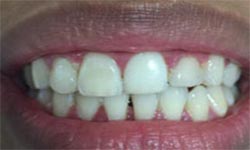

(4) Diastema Closure

Before Treatment

After Treatment

Patient with a complaint of a gap in between upper central incisors. Dental Veneers done to close the gap between the central incisors